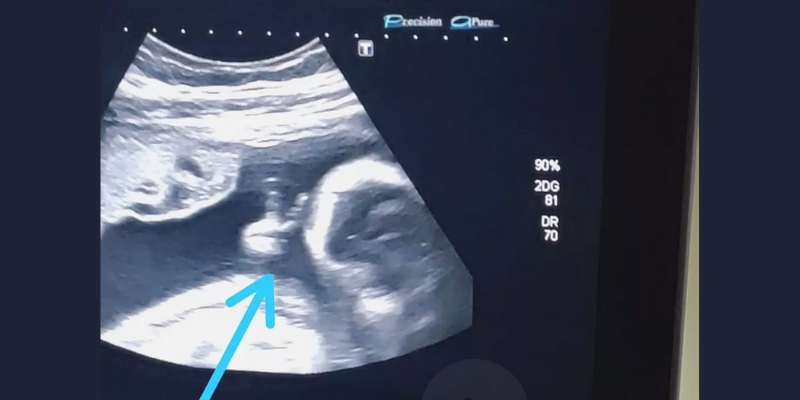

Este motivo hizo que se haya perdido muchas de las ecografías, pero en la más reciente, su hijo David le dio una señal esperanzadora. Primero, futuro papá se emocionó al escuchar los latidos, aunque un gesto se llevó todo su amor.

Mientras el obstetra filmaba los movimientos del bebé, este puso los dedos en forma de “v”. “No podía creerlo”, contó Dos Santos, “pero incluso el médico dijo: ‘Mirá, hizo el símbolo de la victoria con la mano‘”.